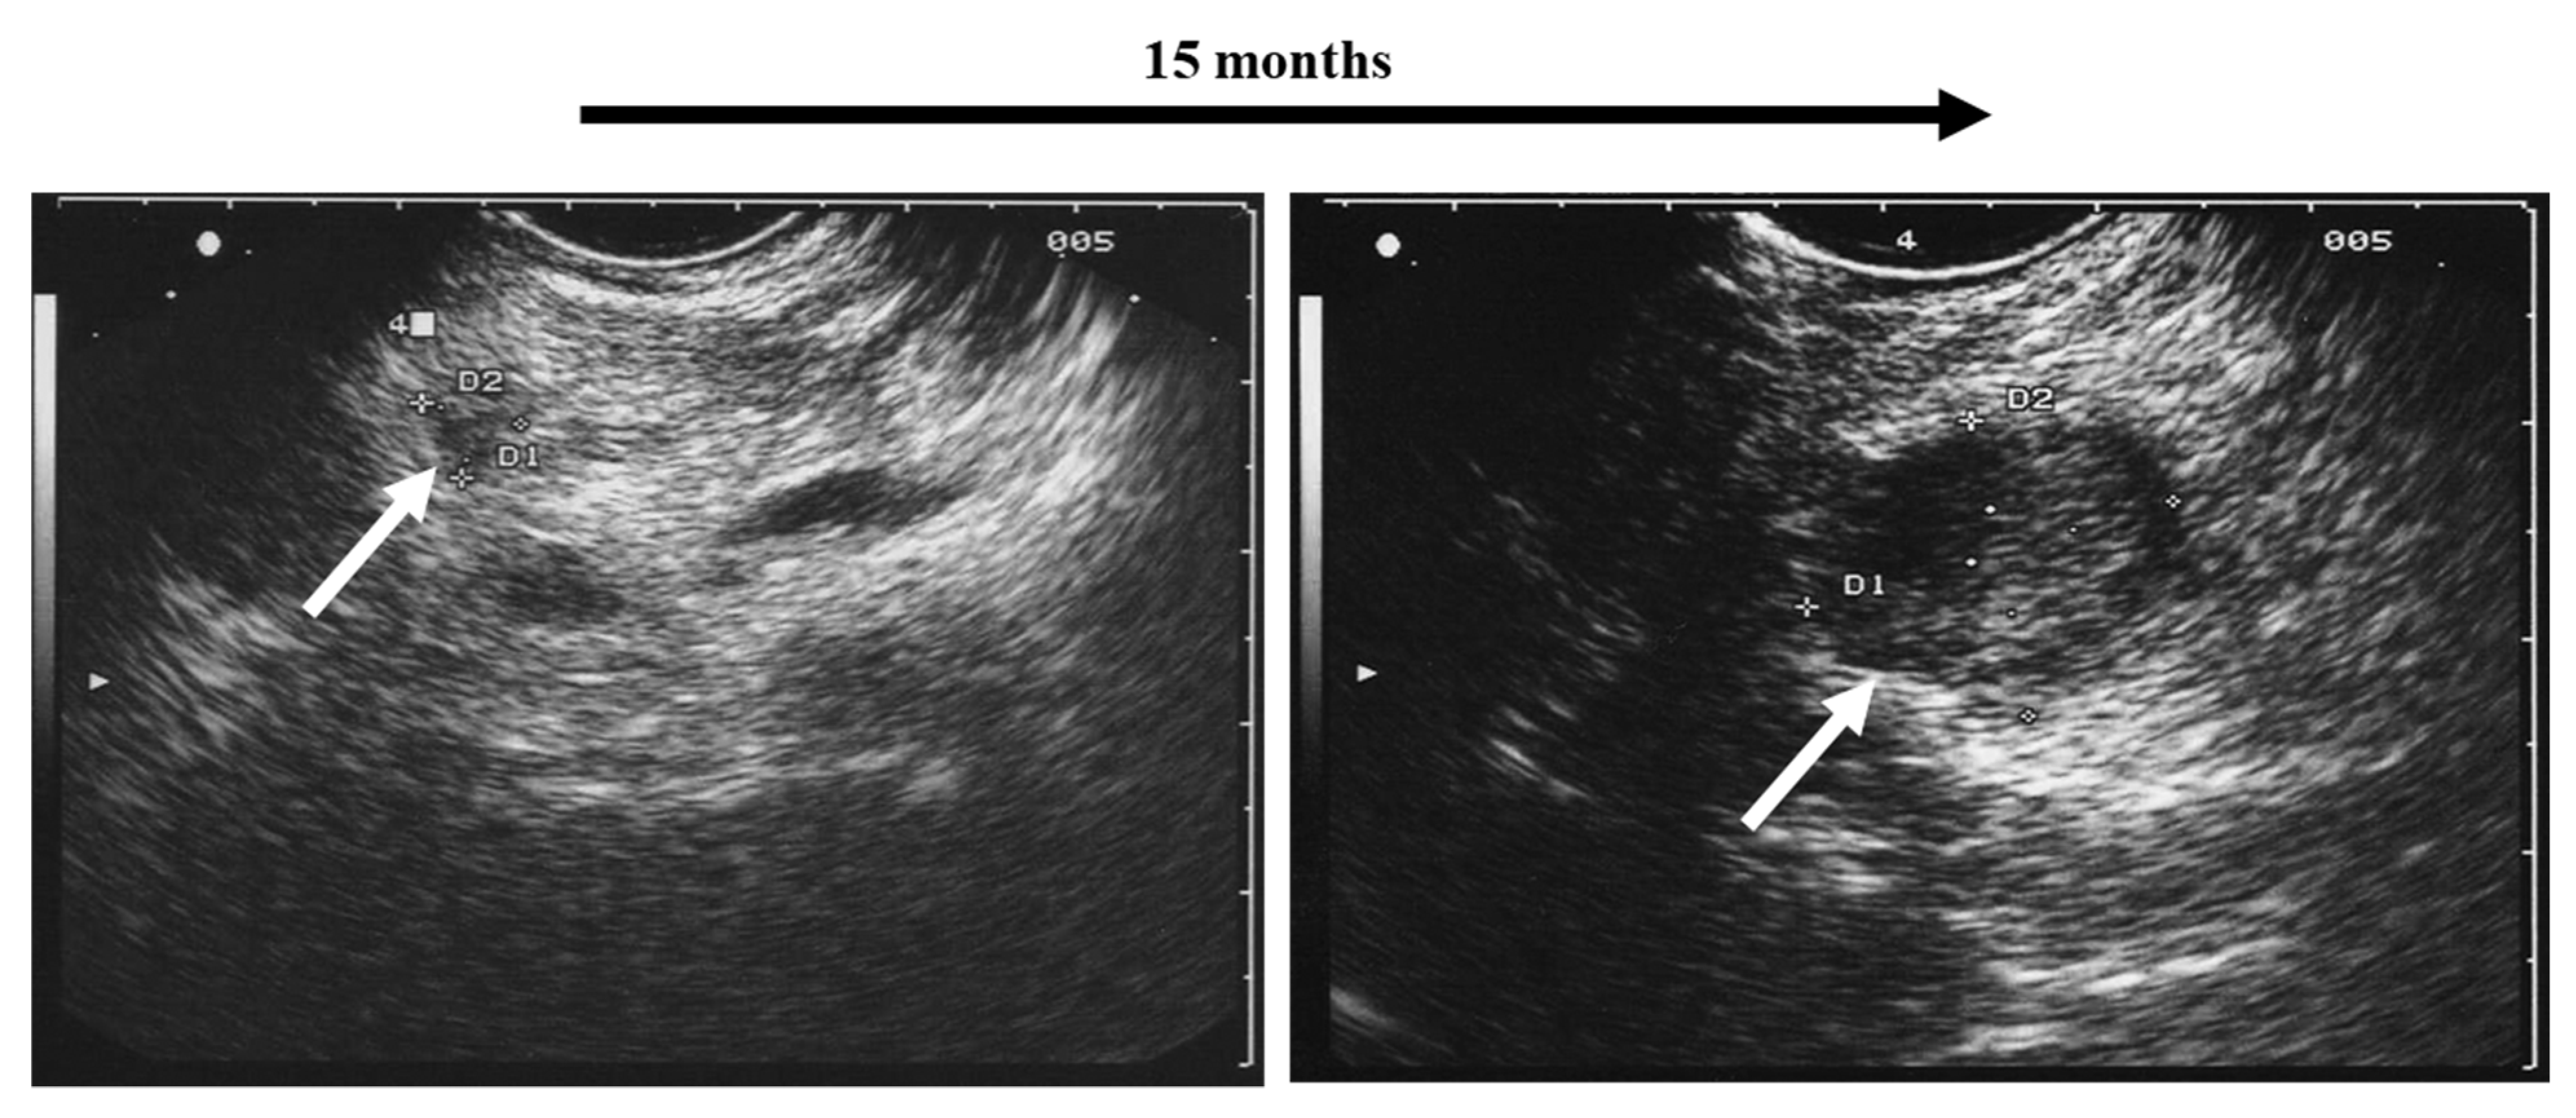

| hypoechoic echogenicity | 82% |

| largely homogenous echostructure | 72% |

| hyperechoic capsular tumor margin | 93% |

| termination of medullary echo at tumor margin | 97% |

| diameter ≤ 2 cm | 77% |

| no/only discrete hyperperfusion (duplex) | 94% |

| tumors fulfilling at least four criteria | 98% |

| tumors fulfilling at least five criteria | 91% |